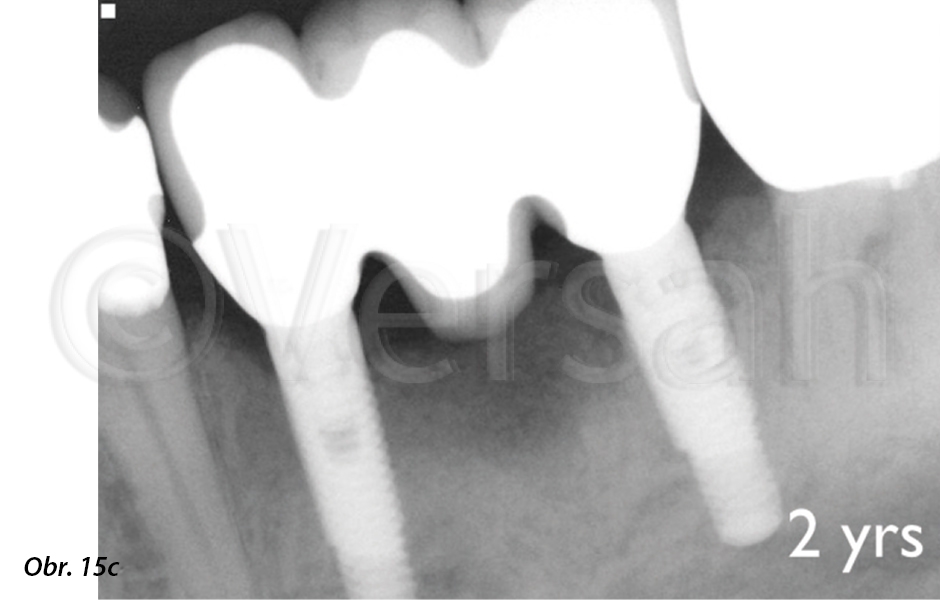

Kontrolní radiografické vyšetření po 2 letech ukázalo stabilní úroveň krestální kosti

V tomto případě oseodenzifikace využívající technologii Densah™ Bur usnadnila expanzi alveolárního hřebene s udržením jeho integrity, a to umožnilo zavedení celého implantátu do vlastní kosti bez jakékoliv expozice při dosažení adekvátní primární stability (obr. 15c, d). Navzdory omezené kostní nabídce, zachovala oseodenzifikace kostní objem a zkrátila čekací dobu na protetickou rekonstrukci. Bez použití techniky oseodenzifikace by takové ošetření probíhalo třemi fázemi léčby v celkové délce 30–50 týdnů: